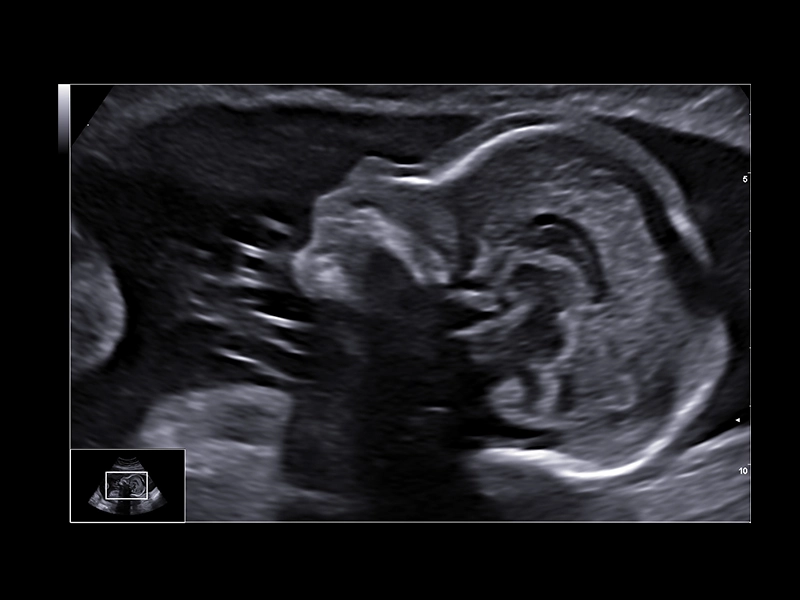

MyLab™9 Platform - Real-time baby face with 4D imaging

MyLab™9 Platform - Real-time baby face with 4D imaging